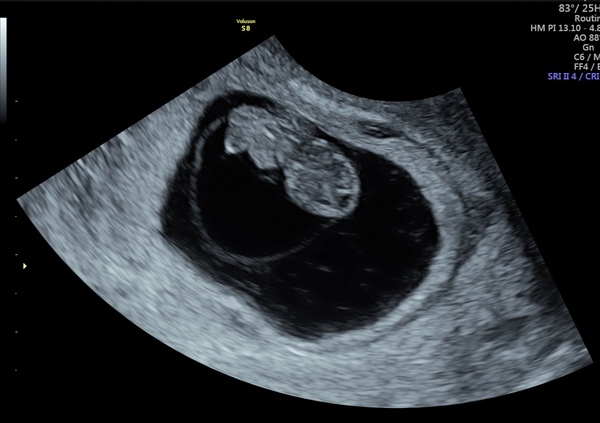

One baby, with a heartbeat, in the right place ☺️ the relief is absolutely huge. I'm a bit numb to be honest, I thought I'd feel happier but it brought up a lot of sadness, especially looking at the scan seeing a baby with plenty of room in the sac. After my waters went, my last few scans were awful, it was around the time everyone in my May group were having gender scans and posting scan photos with babies surrounded by fluid, and mine had none. Sorry to be so negative. I am genuinely over the moon that everything is ok in this pregnancy, I just wish I could feel a bit happier about it.

Oh huge congratulations @imisscoffee! 🎉🎉 Lovely scan picture, you've been through so much it's entirely understandable how it's a bittersweet moment ❤️